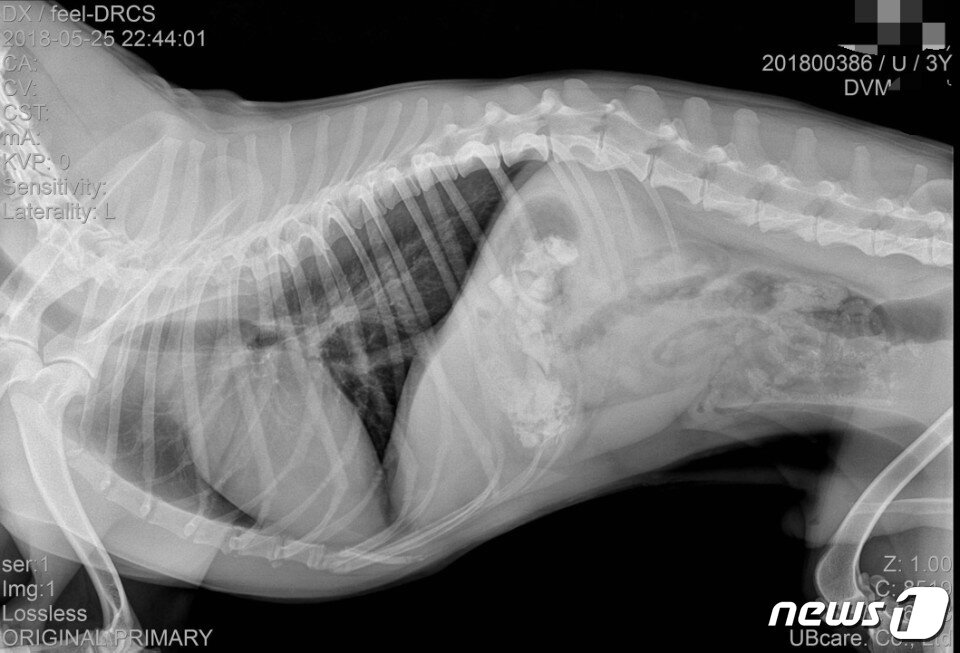

본문 이미지 - 엑스레이에서 발견된 감자탕 뼛조각(사진 김씨 제공).ⓒ News1

엑스레이에서 발견된 감자탕 뼛조각(사진 김씨 제공).ⓒ News1